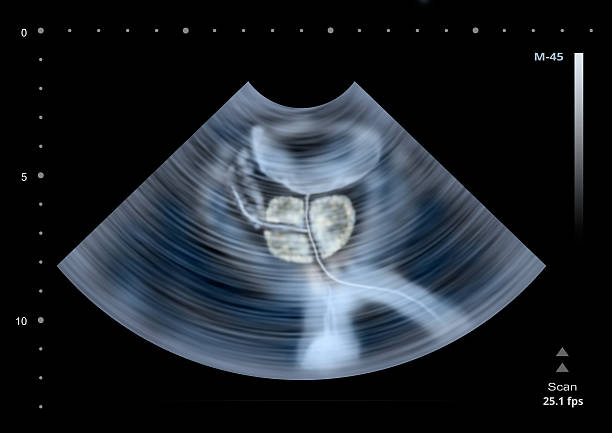

전립선암은 초기에는 증상이 거의 나타나지 않아 발견이 어렵습니다. 하지만 조기에 검진하여 발견된 전립선암의 경우 치료 가능성이 높아집니다. 따라서 전립선암 초기 증상을 알아두고, 정기적인 검진을 받아야 합니다. 이는 특히 합병증 예방을 위해 보다 중요한데 립선암은 진행되면서 합병증을 일으킬 가능성이 있습니다. 예를 들어, 골다공증, 방광 기능 장애, 성기능 장애 등이 그 예입니다. 따라서 초기에 전립선암을 발견하여 합병증 예방을 위한 조치를 취할 필요가 있어 이번 시간에는 전립선암 초기증상에 대해 자세히 알아보겠습니다.

전립선은 방광 주위에 위치하여 방광의 출구를 둘러싸고 있습니다. 전립선암이 발생하면 종양이 전립선을 압박하여 방광의 기능을 저해할 수 있습니다. 이로 인해 방광이 완전히 비어지지 않고 남아있을 수 있어 소변을 제대로 제어하기 어려울 수 있습니다. 이로 인해 요실금이나 배뇨 중 통증을 경험할 수 있습니다.

전립선은 방광과 직접적으로 인접해 있으며, 전립선암 초기에는 전립선의 세포가 방광으로 침범하여 방광 축농증이 나타날 수 있습니다. 이로 인해 배뇨 어려움과 방광에 담긴 소변의 양이 적어지는 등의 증상이 나타날 수 있습니다.